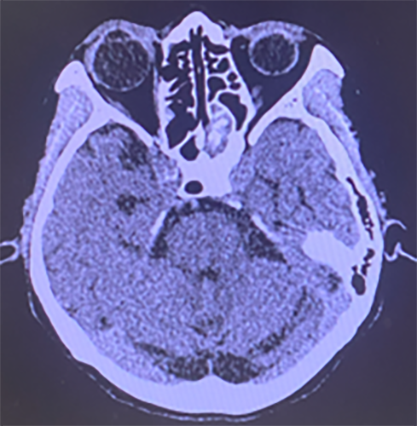

頭蓋内合併症(CT)

CTにて頭蓋内合併症が疑われる。